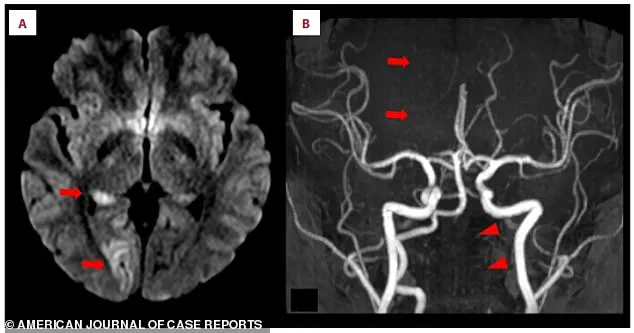

Doctors, upon examining her brain scans, discovered acute ischemic stroke in the right occipital lobe, a region critical for visual processing.

The MRI images, marked with arrows, revealed bright white spots—evidence of brain tissue deprived of oxygen due to blocked blood flow.

The scans also exposed a more ominous detail: a missing section of the right posterior cerebral artery, the key blood vessel supplying the brain.

This artery, normally a smooth, continuous line, had a distinct gap, indicating a blockage.

To address the crisis, doctors performed a thrombectomy—a procedure that involved threading a thin tube through an artery in her groin and guiding it up to the clot in her brain.

Using a specialized device, they extracted the clot, restoring blood flow almost instantly.

To ensure complete removal of the clot, doctors followed the thrombectomy with intra-arterial thrombolysis, administering a clot-busting drug directly to the site of the blockage through the same catheter.

This dual approach maximized the chances of dissolving any residual fragments and preventing further complications.